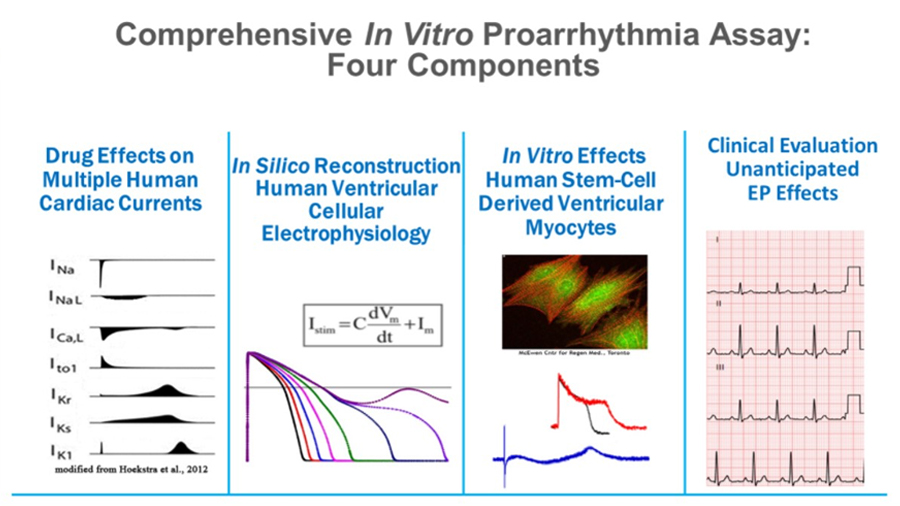

The NOVA team has been involved in ion channel research since the 1980’s. They have a long history of providing data for regulatory guidelines. For instance, we conducted the hERG screening for the original ILSI/HESI safety study which became the groundwork for the current S7B guidelines, and members of our team have been contracted by the FDA to provide ion channel screening in support of the new CiPA safety assessment guidelines. NOVA has worked with 100’s of companies along with multiple government agencies to help de-risk compounds.